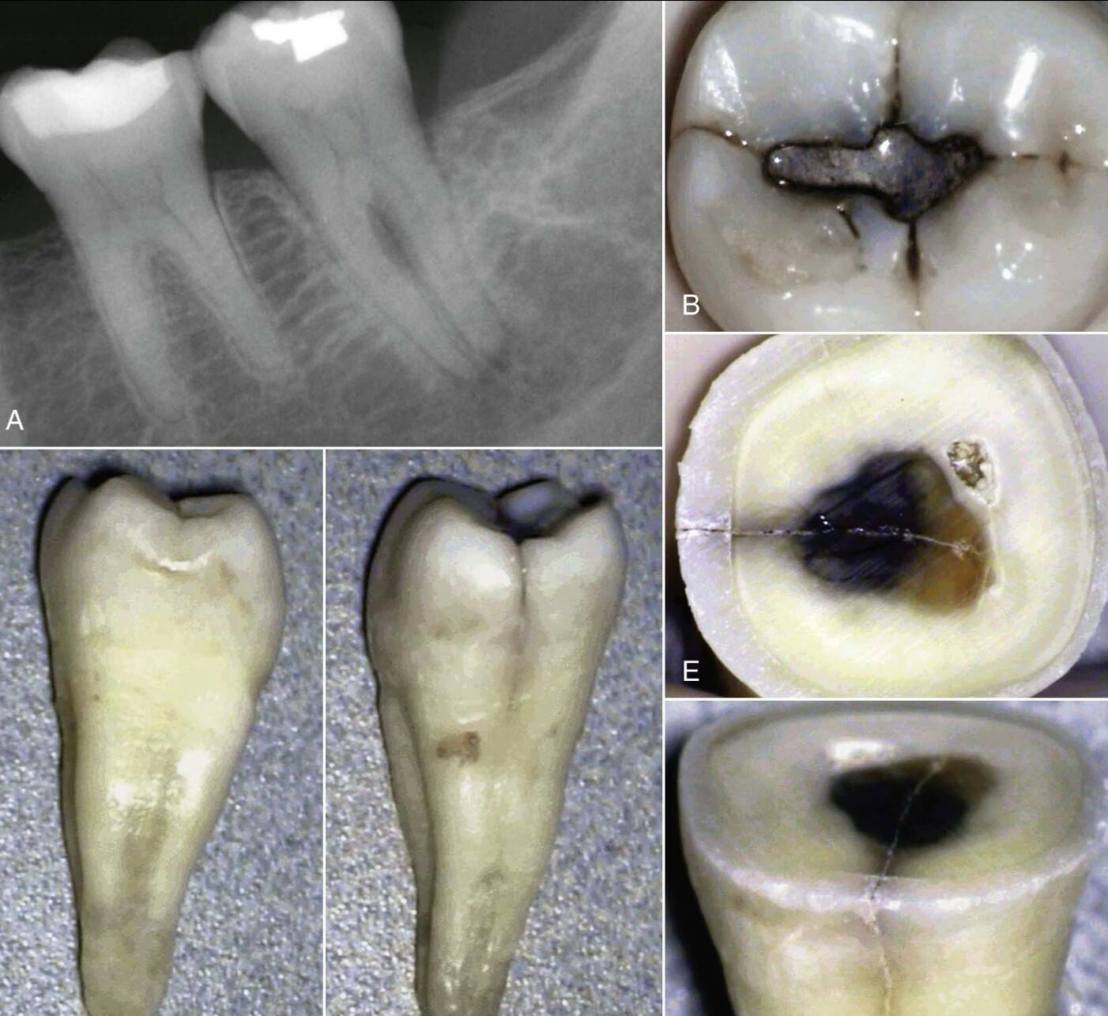

เท่าที่เจอมา ใน case ที่ filling ไปดีมาก แต่วัสดุอุดหลุดออกมาโดยหาสาเหตุไม่ได้ครับ ใน case เหล่านี้ ฟันอาจมีชิ้นส่วนที่ขยับจากรอย crack จนทำให้วัสดุค่อยๆ loose และหลุดออกมาในที่สุด

อีกกรณีที่ต้องคำนึงถึง คือ ทดสอบได้ว่าฟันมี pulp necrosis โดยไม่พบข้อบ่งชี้เฉพาะ ไม่พบ deep caries หรือ มี filling ที่ตื้นมาก แต่ฟันกลับตาย (ในรูป ด้าน Distal ของ root พบ Oblique vertical root fracture)

อีก case สังเกต filling ตื้นมาก แต่ฟัน non-vital และพบรอย crack ทางด้าน distal เมื่อถอนออกมาแล้ว